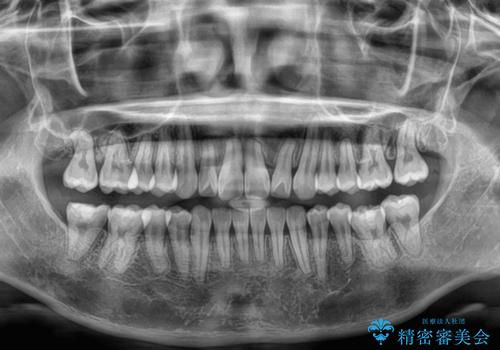

右上と左下の第一大臼歯2本が周辺の歯と比べて位置がずれていたため、ゴムかけやワイヤーに曲げを入れることで移動を試みましたが、どうよら癒着をしており、移動困難と判断されました。

見た目や咬み合わせに違和感がないとのことで、癒着歯の無理な移動は試みずに治療を終えることとしました。